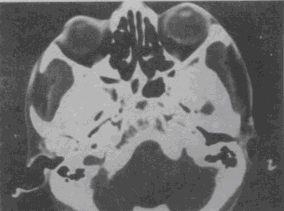

男,37岁,半年来视力下降明显,近1个月失明,CT如图,最可能的诊断是

A.色素膜黑色素瘤伴视网膜脱离

B.色素膜血管瘤伴视网膜脱离

C.色素膜转移瘤伴视网膜脱离

D.色素膜神经瘤伴视网膜脱离

E.黑色素细胞瘤伴视网膜脱离

[单选题]男,37岁,半年来视力下降明显,近1个月失明,CT如图,最可能的诊断是A.色素膜黑色素瘤伴视网膜脱离B.色素膜血管瘤伴视网膜脱离C.色素膜转移瘤伴视网

[单选题]男,37岁,半年来视力下降明显,近1个月失明,CT如图,最可能的诊断是A.色素膜黑色素瘤伴视网膜脱离B.色素膜血管瘤伴视网膜脱离C.色素膜转移瘤伴视网膜脱离D.色素膜神经瘤伴视网膜脱离E.黑色素细胞瘤伴视网膜脱离